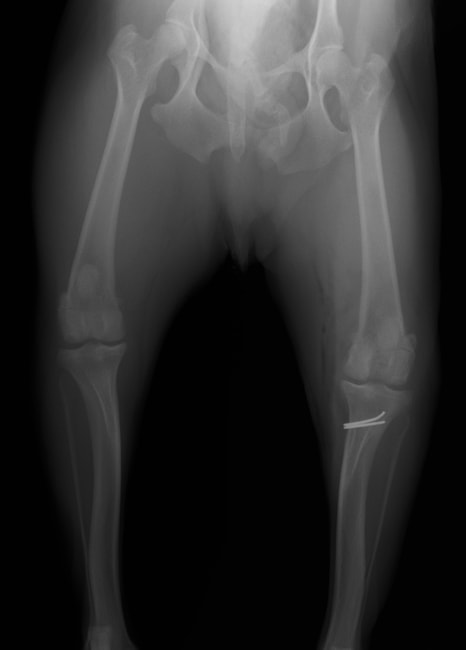

■ 症例22 ポメラニアン 1歳5か月 去勢雄

左後肢の挙上を主訴に来院した。整形学的検査、レントゲン検査より左右の膝蓋骨脱臼(左GradeⅡ〜Ⅲ、右Grade Ⅱ)を認めた。また、脛骨の前方引き出し試験の際に、引き出し兆候は認められないものの、疼痛が認められたため、前十字靭帯の損傷が疑われた。術中における、目視および関節内の操作によって、前十字靭帯の損傷や過伸展といった異常が認められなかったため、膝蓋骨脱臼の整復のみ実施した。手術手技は縫工筋及び内側広筋の解放、脛骨粗面の外側転位、滑車ブロック形造溝術、内外側関節包の縫縮を実施した。本症例は跛行もなく経過良好である。しかし、頸骨高平部の角度(TPA)が 右26.2°、左24.9°であり、解剖学的に前十字靭帯損傷のリスクが高いことから今後の経過に注意が必要である。